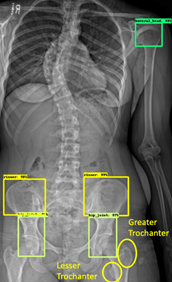

Scoliosis AI

Automatic measurement of spine curves. Limited generalizability.

A. Ha, B. Do, et al.

Skeletal Maturity

Skeletal Maturity Extraction

Automatic Extraction of Skeletal Maturity from Whole Body Pediatric Scoliosis X-rays.

Audrey Ha, John Vorhies, et al.